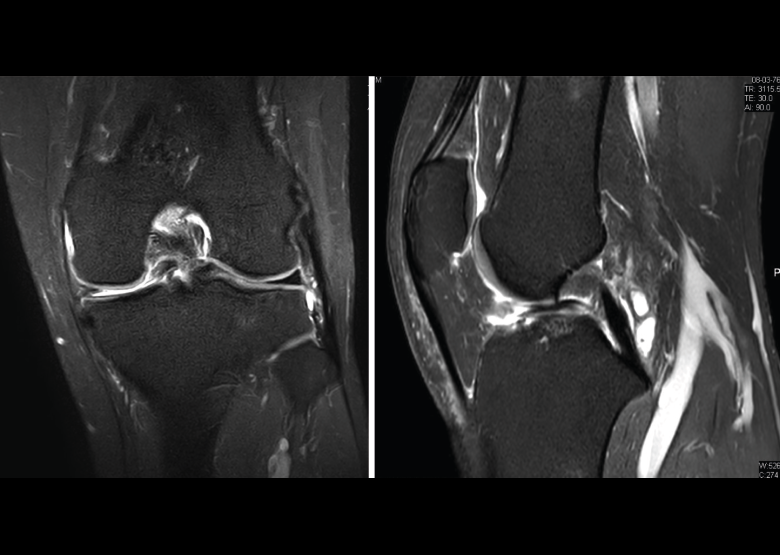

Figura 34. Corte de secuencia sagital T2 Fat-Sat de resonancia magnética de rodilla: rotura en asa de cubo desplazada al asta anterior del menisco externo.

Figura 35. Corte de secuencia coronal y sagital de resonancia magnética de rodilla: rotura en asa de cubo del menisco interno con fragmento desplazado al intercóndilo.

La RM es la técnica de elección en el diagnóstico de la patología meniscal(17)(Figuras 30, 31, 32, 33, 34 y 35).